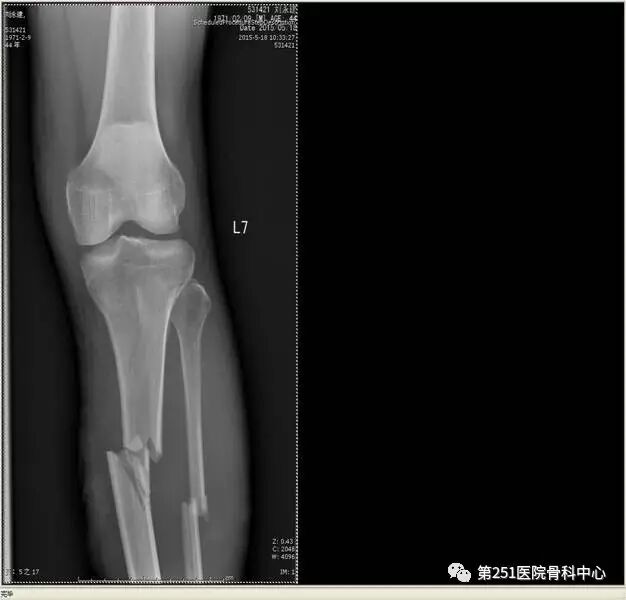

病例2:男性,44岁,车祸伤,双侧胫腓骨骨折(左侧)。